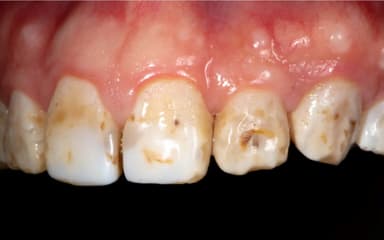

Nguyên nhân gây sâu răng có thể bắt nguồn từ chính chế độ chăm sóc, sinh hoạt hàng ngày

2. Những yếu tố dễ khiến răng cửa bị sâu

Việc răng cửa bị sâu thường dễ xảy ra do một số yếu tố sau:

– Thói quen vệ sinh răng miệng kém: Việc không đánh răng và sử dụng chỉ nha khoa đều đặn có thể dẫn đến tích tụ mảng bám. Điều này sẽ làm tăng nguy cơ sâu răng cửa.

– Chế độ ăn không đảm bảo, không lành mạnh: Chế độ ăn nhiều đường có thể tạo điều kiện cho vi khuẩn sâu răng phát triển mạnh mẽ. Từ đó, răng cửa sẽ dễ bị vi khuẩn tấn công, dẫn tới sâu răng.

– Hút thuốc lá: Thuốc lá là nguyên nhân gây ra nhiều vấn đề sức khỏe. Trong đó, hút lá nhiều khiến môi trường khoang miệng bị khô. Đây là môi trường lý tưởng để các vi khuẩn sâu răng phát triển, tấn công.

– Thiếu Fluor: Fluor là một loại khoáng chất quan trọng giúp bảo vệ men răng khỏi sự phá hủy của axit, vi khuẩn. Thiếu fluor có thể làm tăng nguy cơ bị sâu răng cửa.